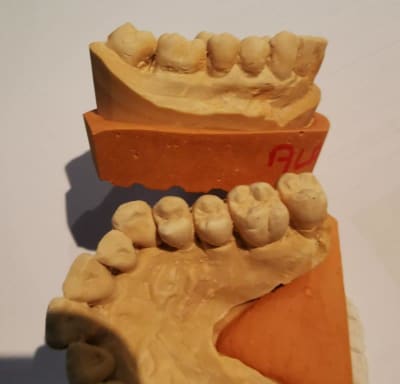

modèles de départ, photos avec le téléphone, désolé, mais ça donne une petite idée

--